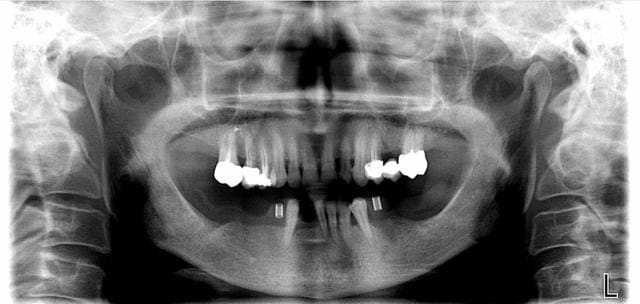

peri-implantite: tourne à gauche?

A votre avis? Je dépose?

Merci de votre sagacité.

2005-2009

Il reste 43 31 32 33 34.